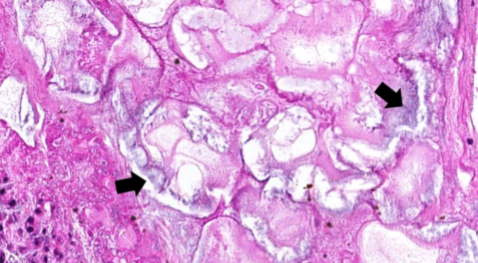

What kind of necrosis is this

FAT NECROSIS

• Shadowy outlines of necrotic fat cells

• Basophilic calcium deposits (fat saponification)

• Inflammatory infiltrate (macrophages, neutrophils)